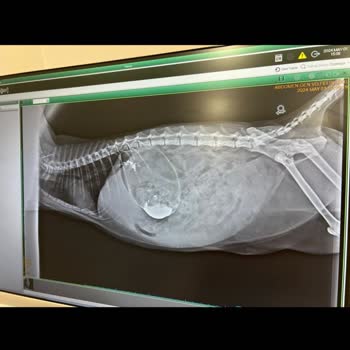

Arlen Veteriner Kliniği Zeytin Yanlış Teşhis Sonucu Vefat Etti

Arlen Veteriner Kliniği, Zeytin isimli evcil hayvanımızın hayatını kaybetmesine sebep oldu. Yanlış teşhis konularak 14 gün boyunca Zeytin'e yanlış tedavi uygulandı. 'Tıkanıklık olabilir mi?' diye sorduğumuzda ciddiye alınmadık. Israrlarımız sonucunda yapılan Doppler ultrasonu ile tıkanıklık tespit e...